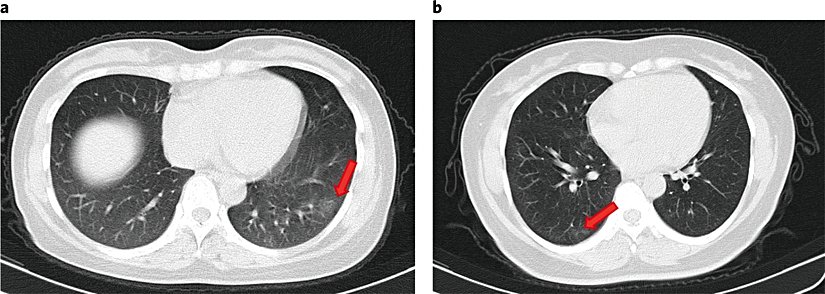

Başvuru üzerine, Toraks BT (bilgisayarlı göğüs tomografisi) taramaları 16 bireyde (16/37, %43.2) herhangi bir anormallik göstermez iken; 11 asemptomatik bireyde (11/37, % 29,7) fokal zemin cam opasiteleri (akciğerde buzlu cam görünümü) ve 10 kişide (10/37, % 27,0) şerit gölgeler ve/veya yaygın konsolidasyon (alveollerde hava boşluklarının yerini püy, sıvı veya hücrelerin alması) gösterdi. Alveollerin iltihaplanması ve şişmesi durumunda çekilen akciğer grafilerinde buzlu cam görüntüsü şeklinde anomaliler olur. Alveollerin iltihaplanmasına neden olan birçok faktör ve hastalık vardır.

5 kişi hastaneye başvurduktan sonraki 5 gün içinde göğüs BT'de fokal zemin cam opasiteleri veya şerit gölgeler geliştirdi. Kritik semptomatik hastalarda görülen tipik değişiklikler olan plevral efüzyon (akciğerde su toplanması), hava bronkogram (bronşlarda dallanan tübüler patolojik görünüm) belirtisi veya genişlemiş lenf nodu yoktu. Asemptomatik bireylerin % 66.7'sinde (14/21) bir akciğer lobunda sınırlı anormal radyolojik bulgu saptanırken, her iki akciğerde % 33.3'ünde (7/21) anormallik vardı.